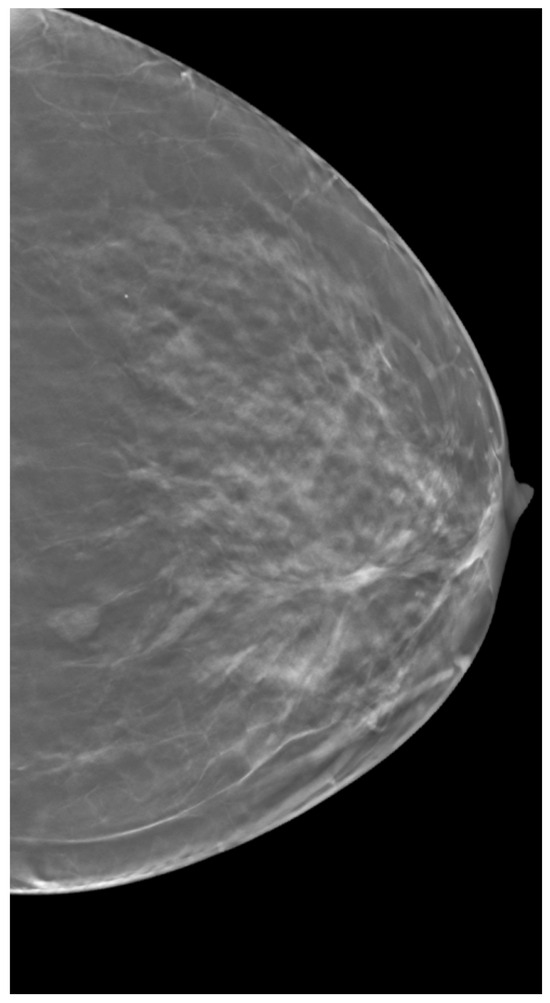

2. Materials and Methods

2.3. Clinical Data

3.3. Breast Density